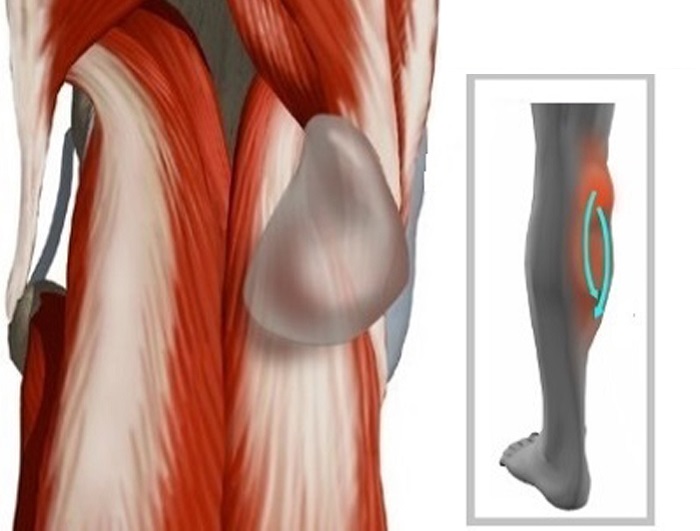

Фото и диагностика кисты Бейкера